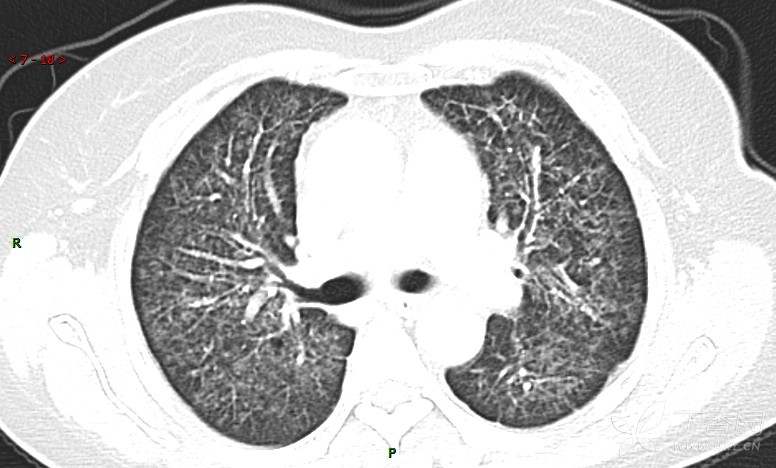

肺内弥漫性网状结节影,PET-CT却无阳性病灶,这是?(附其他2例链接)

女性,58岁,阵发性咳嗽2月,加重1月。

患者于2月前无明显诱因出现咳嗽,以阵发性干咳为主,接触冷空气后咳嗽明显,偶咳少量白色泡沫样痰,咳嗽剧烈时感憋喘,无发热、盗汗,无头痛、头晕,无胸痛、咯血,无恶心、呕吐,无腹痛、腹泻,无尿频、尿痛等不适,于当地医院给予肌注及静脉药物治疗,具体药物名称不详,效果欠佳,近1月来患者咳嗽频率较前增加,咳嗽剧烈时感双侧季肋区疼痛不适,10余天前出现发热,体温在38℃左右,伴畏寒、寒战,无头痛、头晕,无纳差、乏力等不适,药物治疗后体温降至正常,仍阵发性咳嗽,今为求进一步诊治,就诊于我院急诊,因呼吸内科暂无床位,急诊门诊以“肺间质病变”收入急诊留观室,给予“抗感染、止咳”等对症支持治疗后,今日以“肺间质性病变”收入我科,患者自本次发病以来,神志清,精神可,饮食尚可,睡眠一般,大小便正常,体重较前无明显变化。

患者活检肺组织后行PET/CT检查